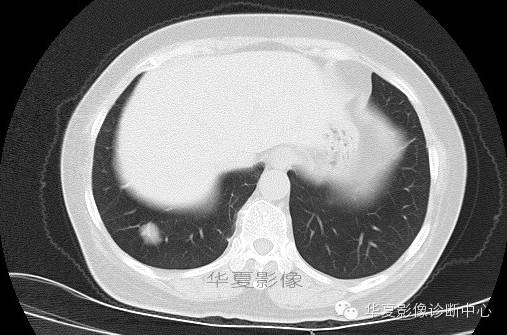

影像资料:

术中切除(右下)部分肺组织7x6x2cm,切面见一灰白色肿物,直径2cm,质较脆,与周围组织界限清,略呈分叶状,无包膜。

(右下肺)错构瘤(以软骨成份为主)

肺错构瘤多发生在胸膜下肺表浅部位,呈球形、椭圆形,有完整的包膜,质硬,易与周围肺组织分开。肺错构瘤的直径0.5~12cm,多数小于3cm。肿瘤剖面呈灰白色,质硬,有黏液和囊腔。主要成分有软骨、腺体、平滑肌、脂肪及纤维组织等。肿瘤可发生钙化,多位于中心,分布较均匀,此种钙化结构常像爆米花样或核桃肉样。